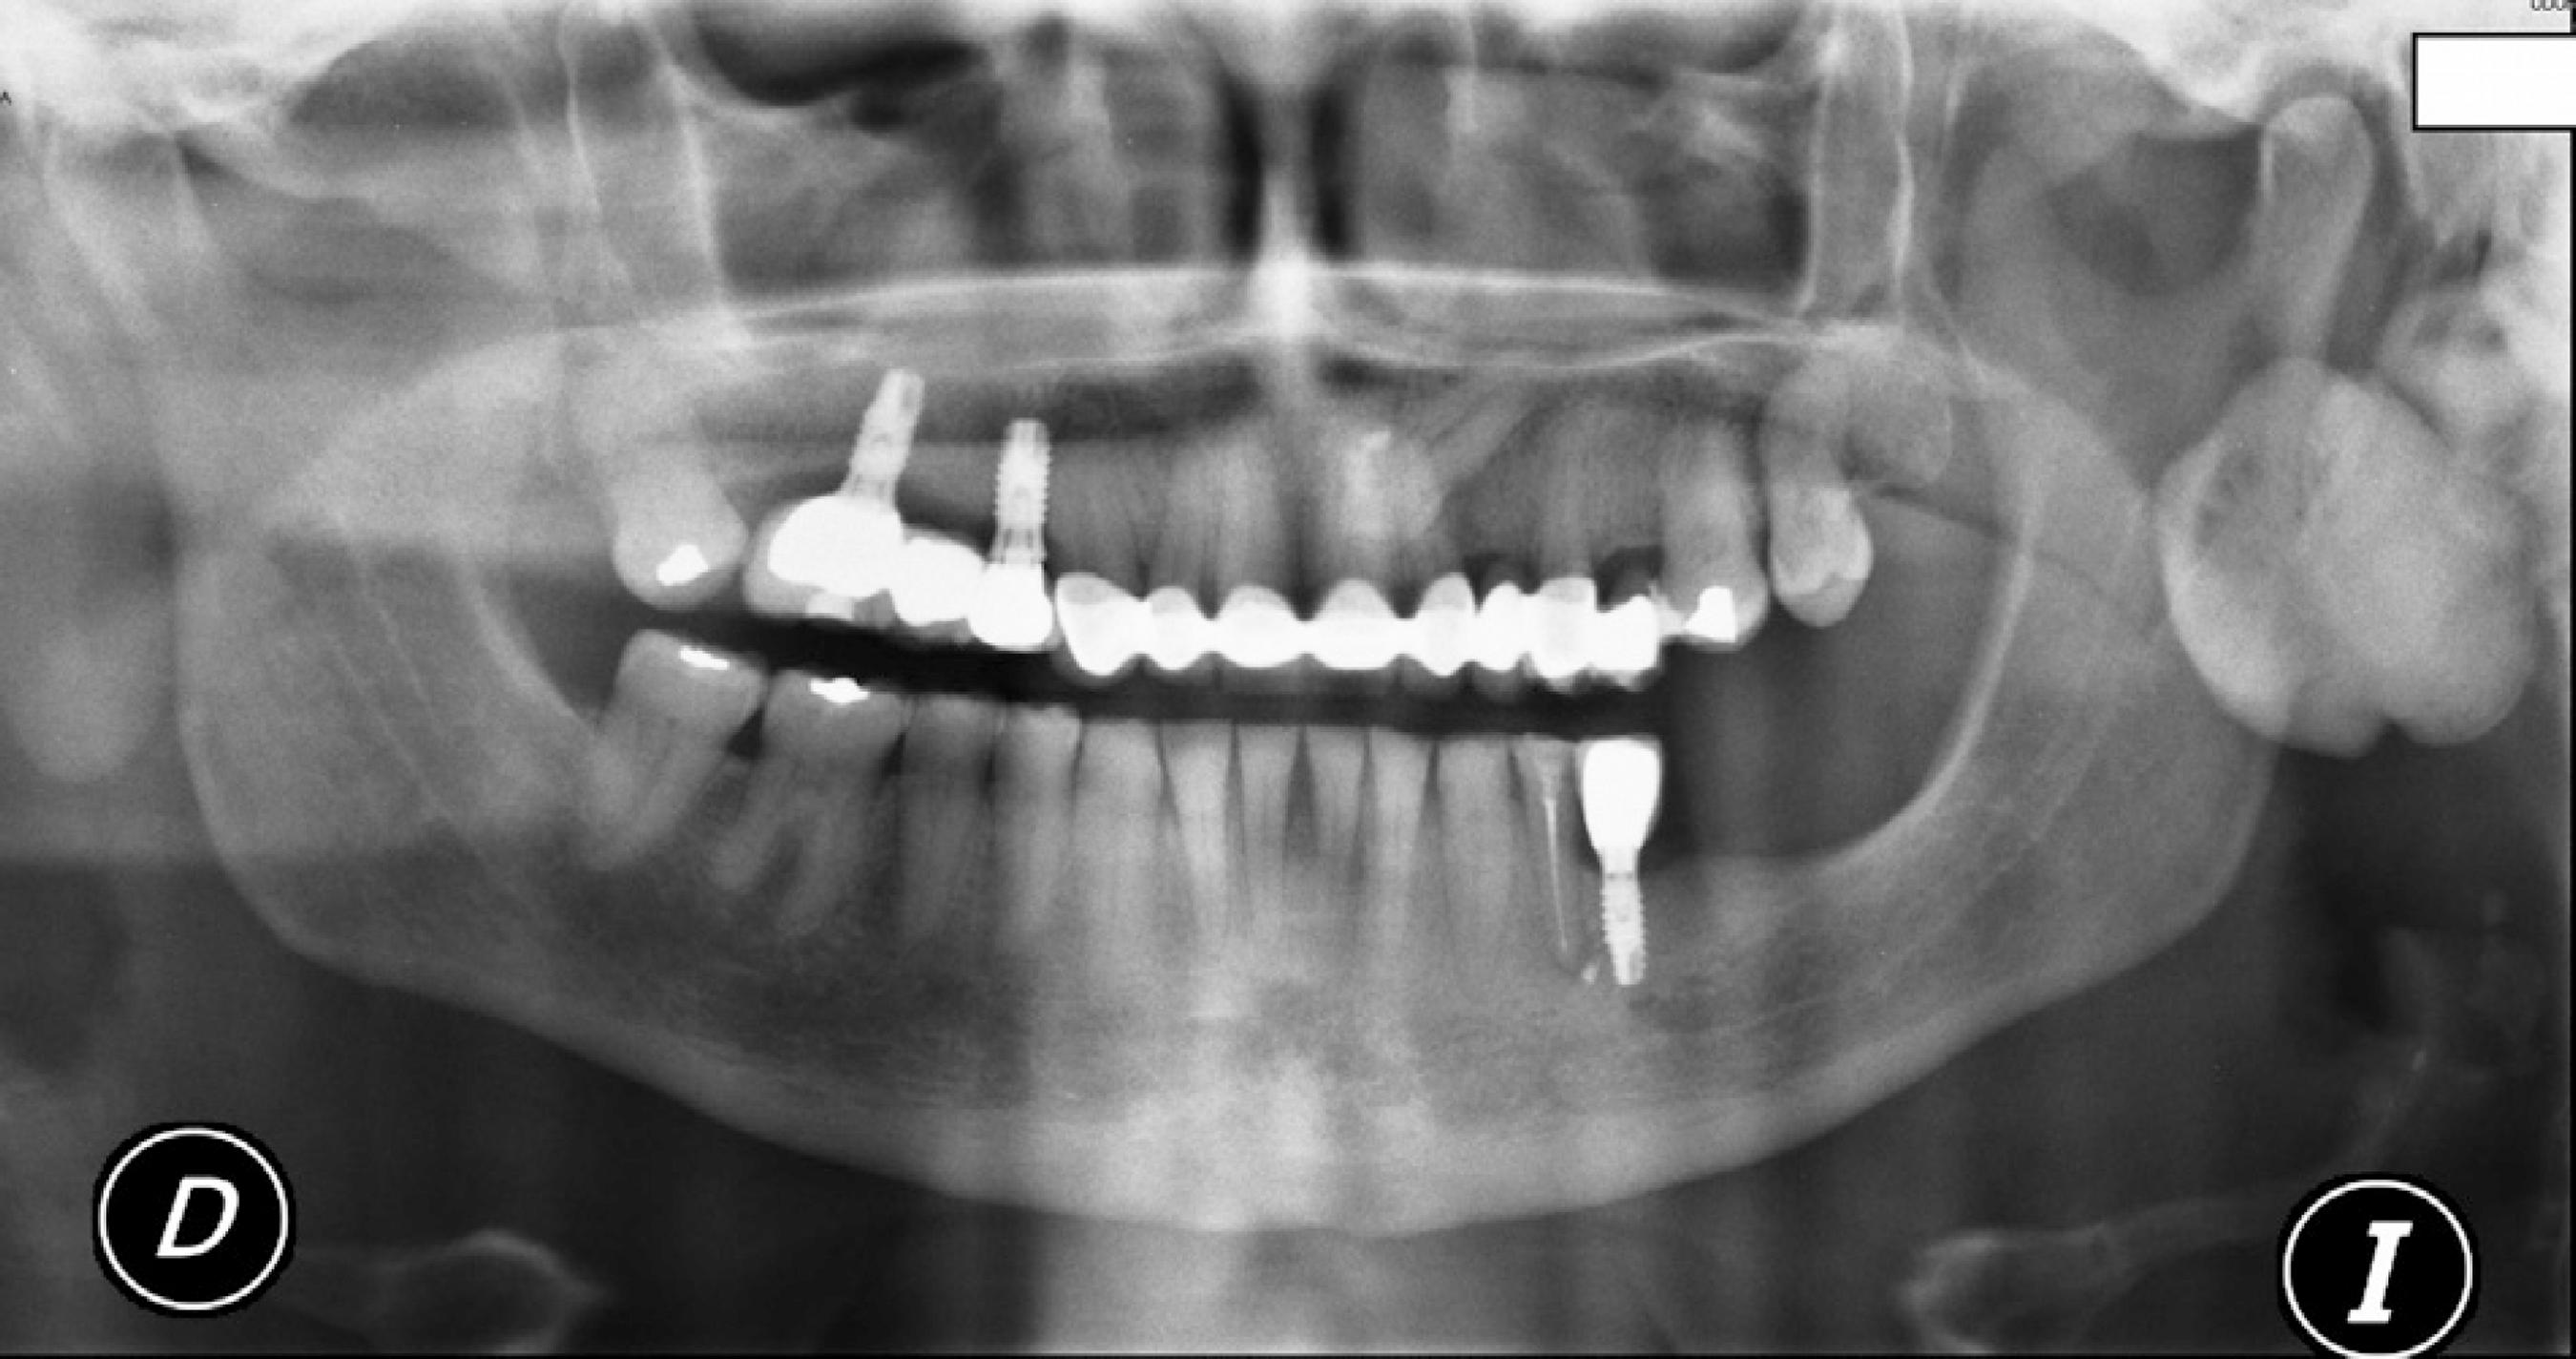

INTRODUÇÃO. O osteoma é uma lesão osteogênica benigna, caracterizada pela proliferação de osso compacto ou esponjoso 1,2,5,7.Histologicamente, pode apresentar- se de três formas: osteoma compacto, que possui pouca quantidade de tecido fibroso; osteoma esponjoso, que tem predominância de trabéculas fibrosas; e osteoma misto, que é uma mistura dos dois tipos 1,2,3,6,7,8.

2. Histological Findings. Histologically, an osteoma is represented as a mass of abnormal dense bone that may originate from the periosteum or from bone marrow, thus differentiating between two types of osteomas [1,2].Compact osteomas, also called "ivory", are made of mature lamellar bone with minimal marrow spaces and occasional haversian canals without any fibrous structure [3,4] (Figure 3).

Osteoma é uma neoplasia mesenquimal benigna, caracterizada pela formação de osso compacto ou esponjoso. A sua etiologia é desconhecida, mas há autores que consideram a lesão como um processo hamartomatoso; enquanto outros, defendem que a sua origem seja neoplásica. A presença de osteomas múltiplos pode ser um indicativo do diagnóstico.